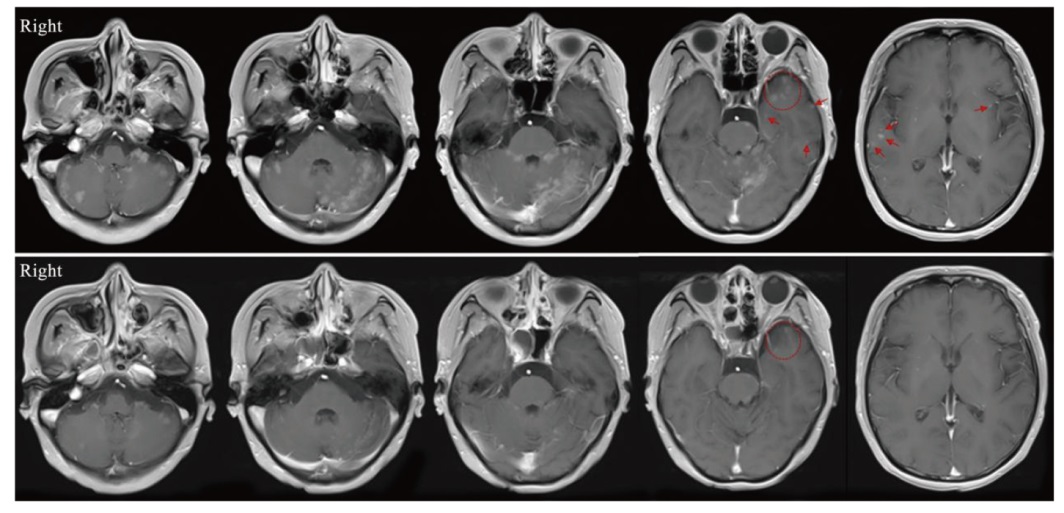

| 图2 第1例患者治疗前后脑磁共振成像对比 |

| Fig. 2 Comparison of brain magnetic resonance imaging before and after treatment in the first patient Red markings indicate lesions that have regressed or disappeared outside the irradiation field. |